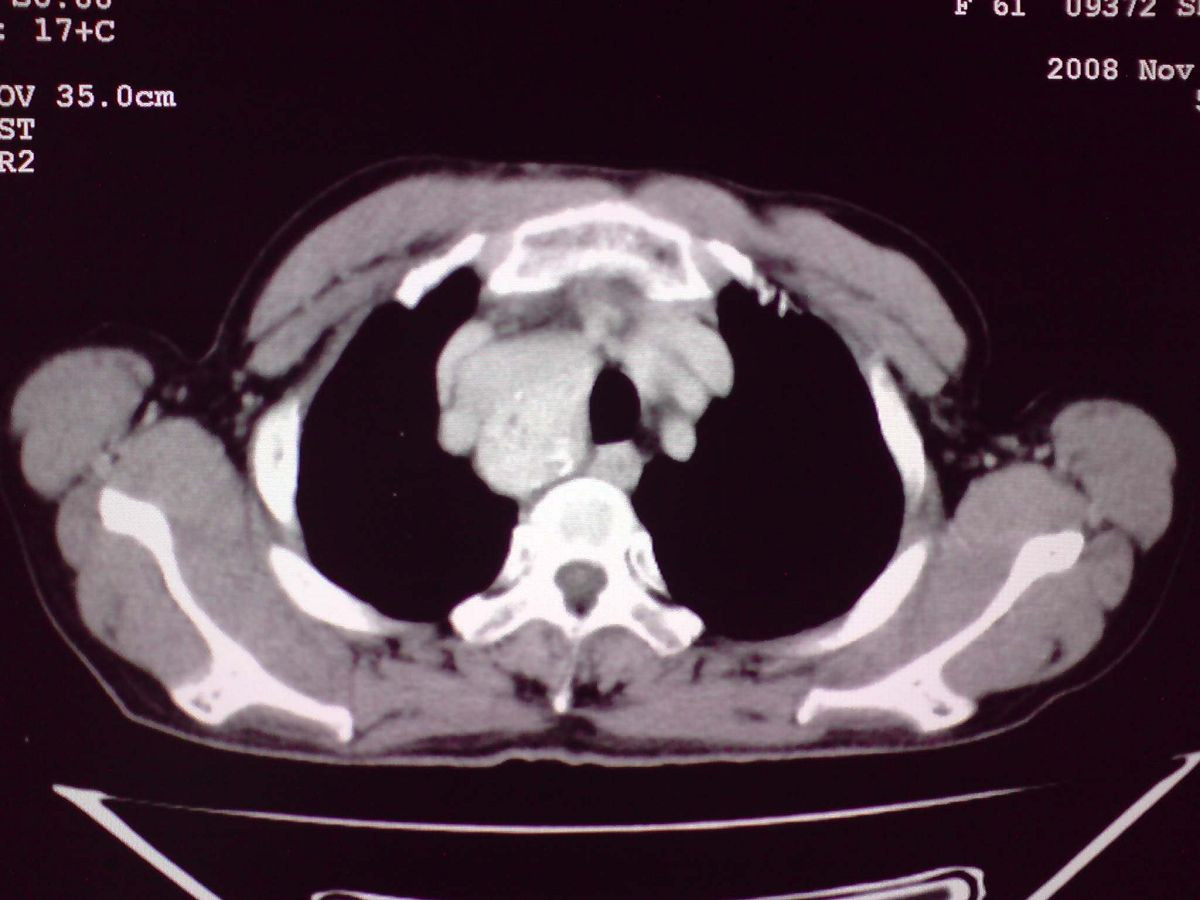

患者女性,65岁,无明显不适,甲状腺功能无异常

双侧甲状腺肿大,向下部分突入胸腔,双侧甲状腺内密度不均,可见结节状低密度影,并见散在斑点状钙化,增强后病灶实性部分强化明显,气管受压稍变窄左移。

考虑:双侧甲状腺腺瘤可能,不除外甲状腺癌。

胸内甲状腺,双侧结节状甲状腺肿伴右侧甲状腺腺瘤。

甲状腺左右叶增大,并向下突入胸腔内,其内可见多发条片状钙化影及囊性低密度影,邻近组织及血管无浸润、包埋征像,双侧结节性甲状腺肿伴右侧甲状腺腺瘤形成可能性大,甲状腺癌待排;因病人就要手术,期待结果。